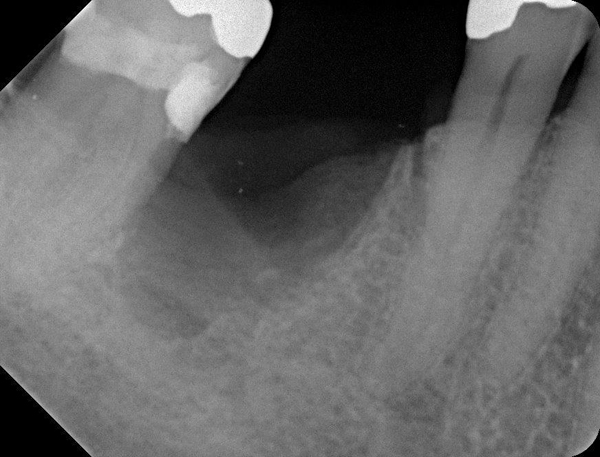

Fig 15. (Case 3) Radiograph of tooth No. 19, which had a hopeless prognosis.

Figure 15

Fig 16. Radiograph of extraction socket. Buccal and lingual plates were defective.

Figure 16